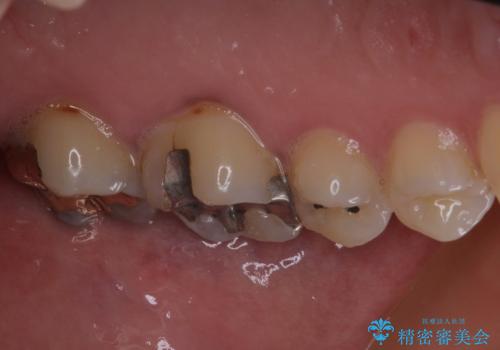

咬み合わせをみると、奥歯に負担がかかりやすいことが分かったので、適合がよく、硬さが歯と近いPGAインレー(白金加金合金インレー)にて修復治療を行うこととしました。

ゴールドインレーは銀歯のインレーやセラミックインレーと比べ、「技工操作の精度が高く、適合が著しく良い」というメリットがあります。特に上の奥歯は歯科医師の操作が行いにくいため、「適合の良さ」は再治療のリスクを防ぐ上でとても重要な要素となります。

上の奥歯は金属色が見えることもないため、審美的な問題は全くありません。